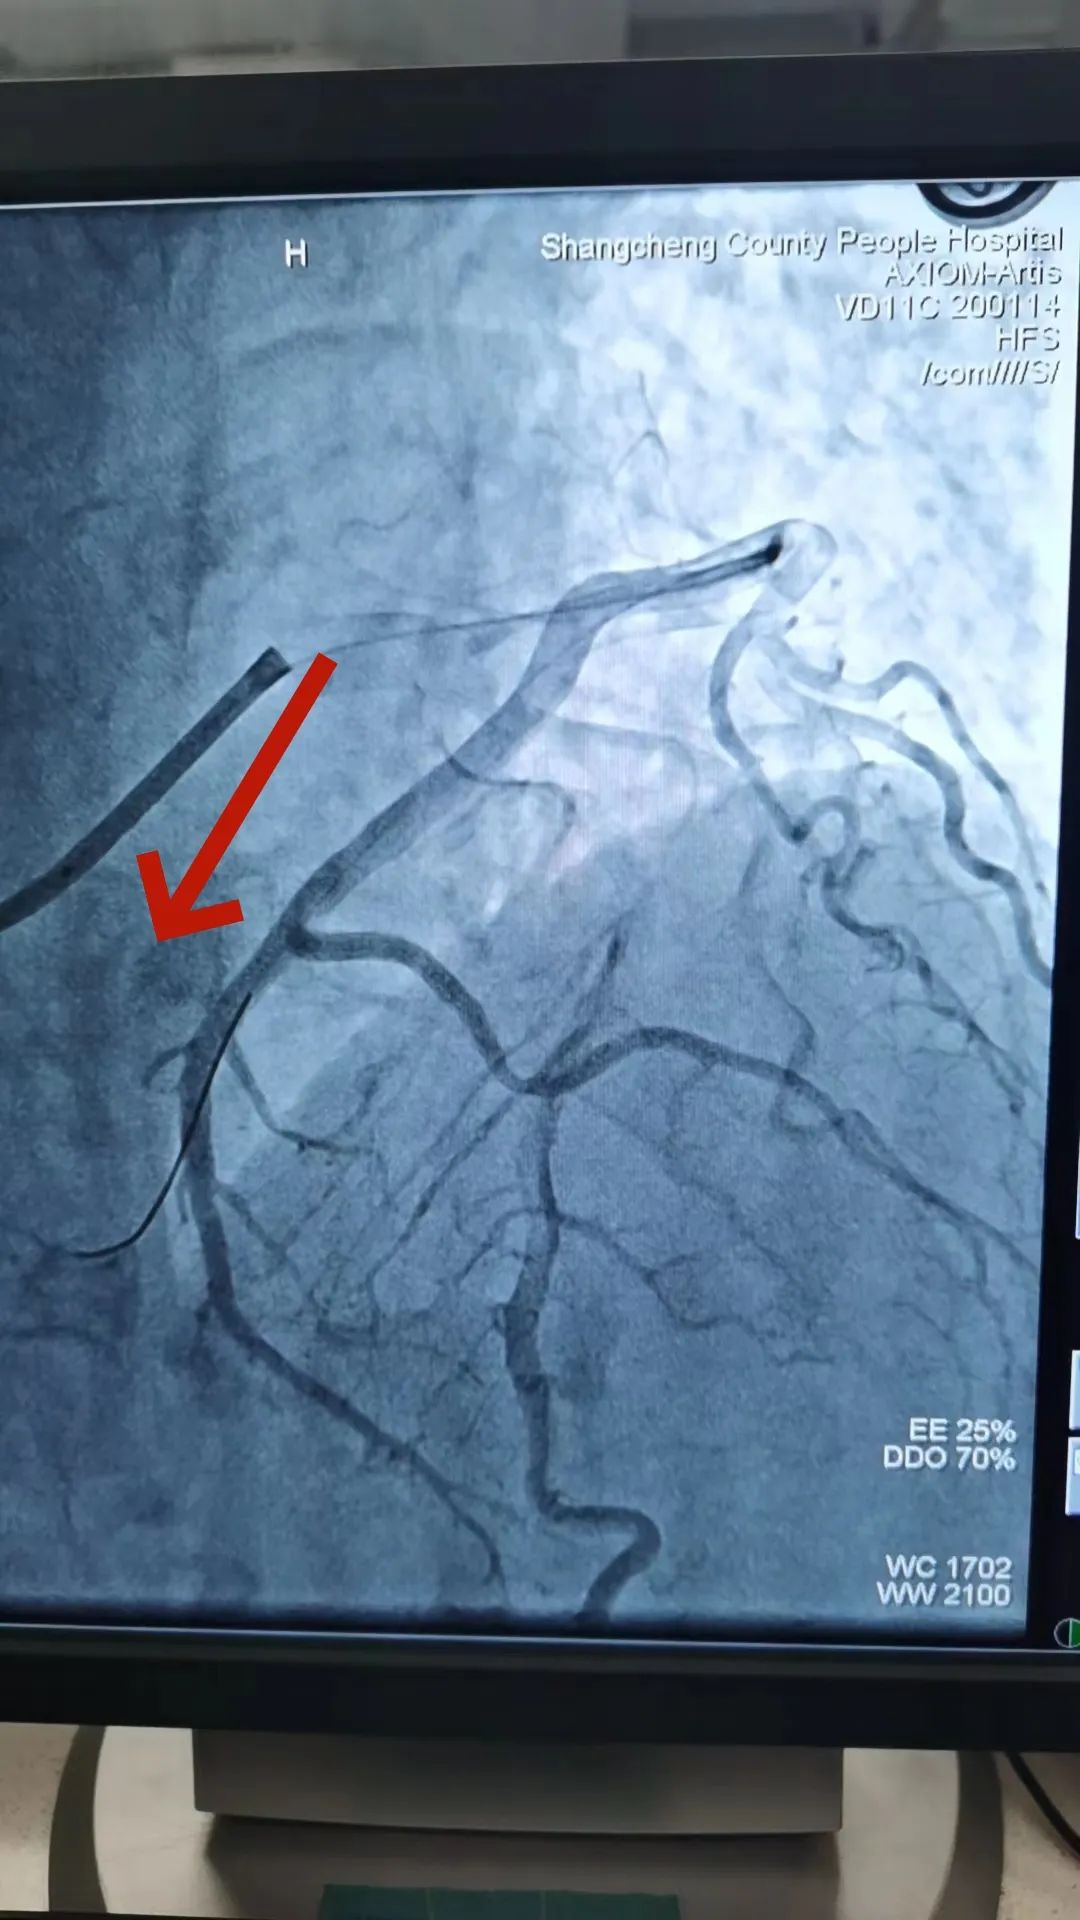

2023-10-19_勇攀“心”高峰——记商城县人民医院心血管内科介入能力再突破!_7.jpg

前降支未见明显狭窄